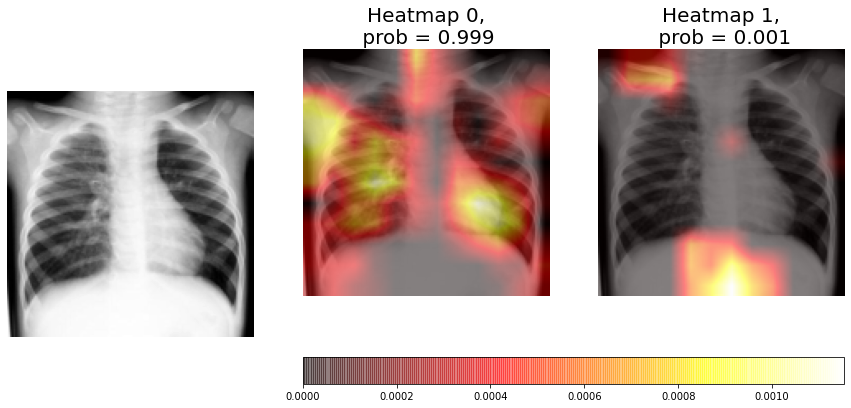

4.2.1 Individual heatmaps

Figure 6 shows the prediction and heatmaps of an individual CNN for a non-consolidation test sample. The non-consolidation probability estimated by the model is 99.9%. If we analyse and compare the heatmaps, we can see that neuron 0 heatmap (non-consolidation) is clearly brighter than neuron 1 heatmap (consolidation), and in neuron 1 heatmaps there are different areas marked that shouldn’t be, corresponding to the clavicle and diaphragm. The conclusion is that the CNN has not found any signs of consolidation, but the previously referred areas of neuron 1 heatmap should not be lighted up.

In Figure 9 we can see that the average heatmap for neuron 0 (non-consolidation class) is much brighter than the average heatmap for neuron 1 (consolidation). If we compare this visualization with the one obtained by an individual CNN (Figure 6), we can see that it analyzes left lung in greater depth than the stand alone model, and focuses on the most relevant features to perform the X-ray classification. It also has a low standard deviation in this area and, unlike the visualization obtained by the individual CNN, it is hardly fixed on the heart area. Therefore, it can be concluded that the ensemble result is better than the one obtained by the individual CNN.